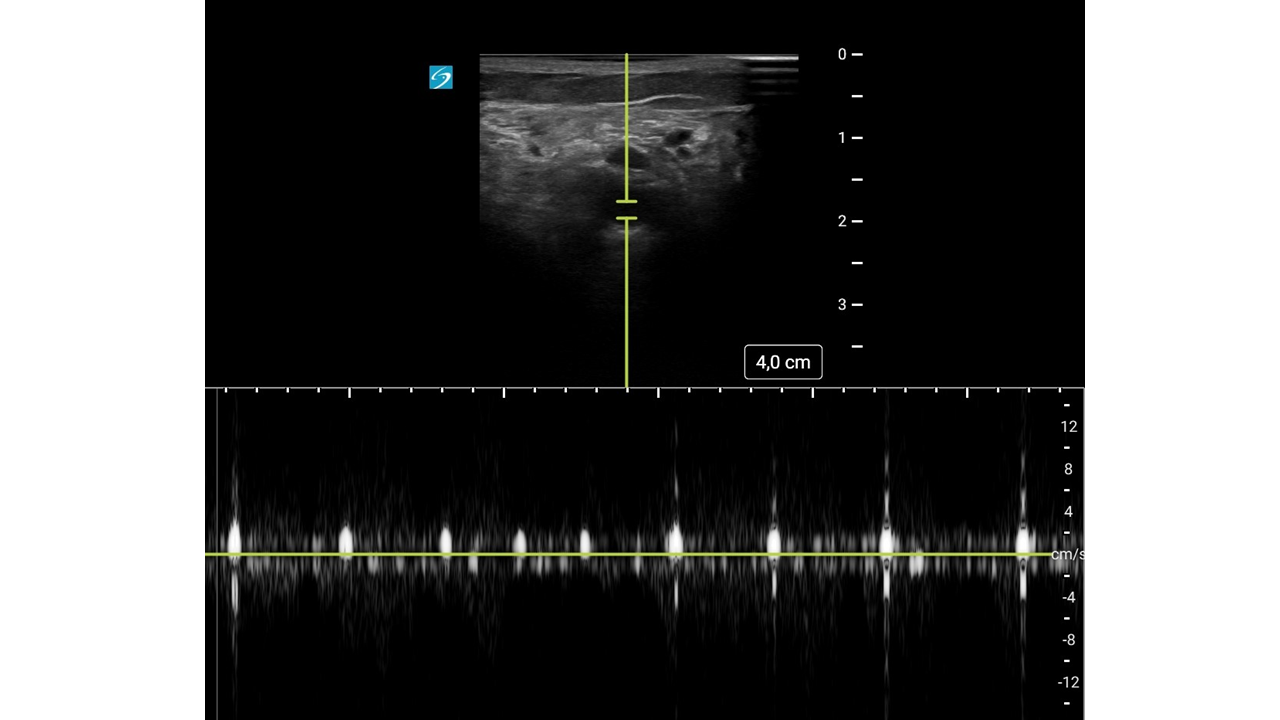

Mujer de 93 años con: fibrilación auricular, enfermedad renal crónica y antecedentes de hemorragias digestivas por las cuales se le había suspendido la anticoagulación oral meses antes.

Motivo de consulta: Dolor súbito, frialdad y pérdida de sensibilidad en la extremidad inferior derecha (EID), con mejoría parcial durante el traslado.

Con mejoría del dolor y pulso poplíteo dudoso, se duda del diagnóstico.

Con sospecha inicial de Isquemia Arterial Aguda (IAA), la mejoría clínica hace dudar abriendo el diagnóstico diferencial a una posible radiculopatía.

Con sospecha clínica de IAA, la ecografía vascular es clave para confirmar el diagnóstico. Su curva de aprendizaje es rápida, se puede utilizar en cualquier punto del sistema y permite derivar al paciente a un centro útil evitando demoras potencialmente fatales.